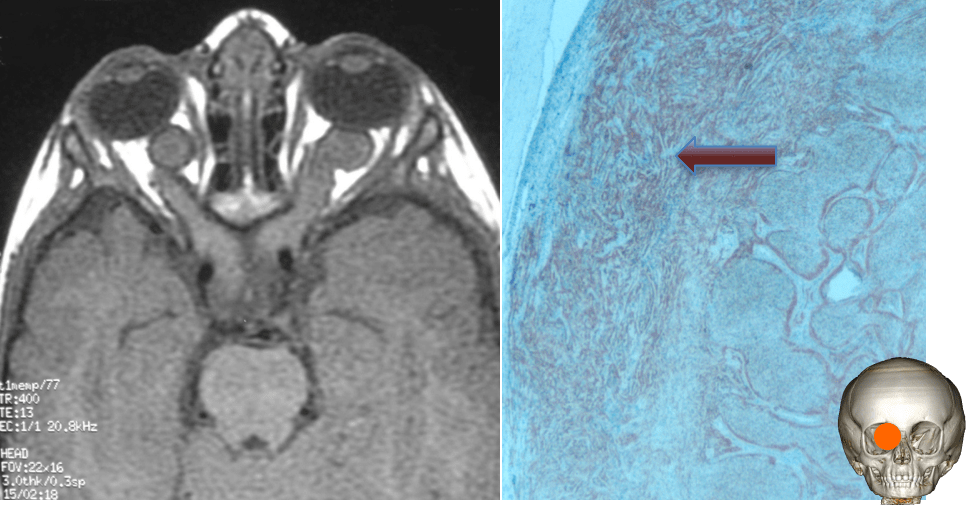

anatomie pathologique

le plus souvent, il s’agit d’un astrocytome pilocytique, rarement d’un gangliogliome

la tumeur infiltre les fibres du nerf, il n’y a donc aucune possibilité de chirurgie conservatrice. Dans la NF1, les cellules tumorales engainent les fibres du nerf, donnant en imagerie un aspect en cocarde.